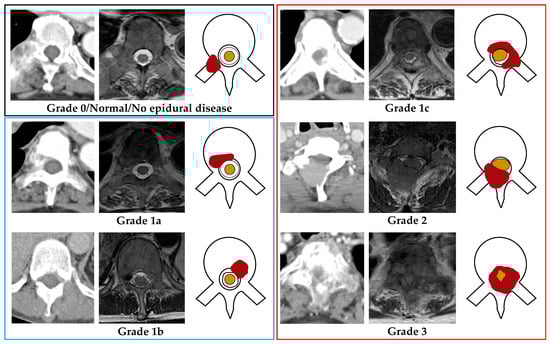

MRI is considered the most accurate imaging modality for the classification of MESCC [11,12]. MRI can provide excellent visualization of vertebral metastatic involvement and any associated malignant epidural disease and its impact on the cerebrospinal fluid space and spinal cord [13]. In cases where MRI is contraindicated, a CT myelogram is another accurate modality for assessing the degree of MESCC. Axial T2-weighted MRI images most accurately characterize the extent of MESCC via the Bilsky grading scale developed by the Spine Oncology Study Group (SOSG) [14,15]. The grading scale uses six groupings, which can be further divided into two key clinical categories; low-grade MESCC (grades 0, 1a, or 1b), which can be treated with radiotherapy (including stereotactic body radiotherapy, SBRT), and high-grade MESCC (grades 1c, or 2, or 3) which can be considered for initial surgery (e.g., separation surgery) and subsequent radiotherapy [16,17,18].

The staging CT dataset was manually labeled for MESCC in consensus by board-certified spine imaging specialists (AM with 7 years of experience and JTPDH with 11 years of experience) and served as the reference standard. The two radiologists labeled each axial CT image in consensus with the corresponding MRI (performed within one month) using an established visual Bilsky SOSG scale (The visual scale is provided in Figure 1).

When inspecting each axial CT image, the radiologists classified MESCC using a three-grade scheme; Normal (no discernible epidural disease or Bilsky grade 0), Bilsky grades 1a or 1b amenable to first-line radiotherapy (low-grade MESCC), and grades 1c or 2 or 3, which more frequently require primary surgical decompression (high-grade MESCC) [14,16]. The visual MESCC grading scale provided to all the radiologists is shown in Figure 1. Degenerative changes (disk bulges, osteophytic change, and ligamentum flavum redundancy/ossification) producing spinal canal narrowing/stenosis were labeled and excluded from further analysis [22,23].

Figure 1. Bilsky grading for metastatic epidural spinal cord compression (MESCC) was demonstrated using axial CT, MRI (T2-weighted), and a picture for each grade (right to left). The red shaded region shows MESCC in each image. Grade 0/normal (Black outline): No metastatic epidural disease present. Low-grade MESCC (Blue outline); Grade 1a: Metastatic epidural soft tissue with no thecal sac deformity, or Grade 1b: Metastatic epidural soft tissue with thecal sac deformity but no spinal cord contact. High-grade MESCC (Red outline); Grade 1c: Metastatic epidural soft tissue touching the spinal cord with no discernible compression or displacement, or Grade 2: Metastatic epidural soft tissue cord compression with some surrounding cerebrospinal fluid still visible, or Grade 3: Metastatic epidural spinal cord compression without discernible surrounding cerebrospinal fluid. Thecal sac = black outline within the spinal canal, Spinal cord = Yellow shaded area within the spinal canal.